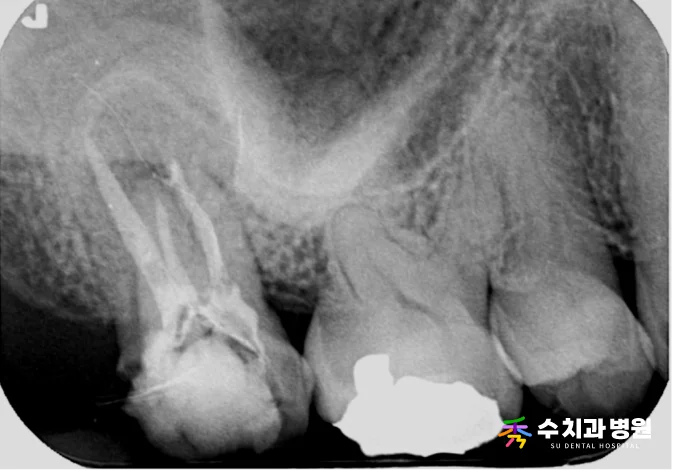

[📸 치료 전 엑스레이] (촬영일: 2023년 8월)

방사선 및 임상 검사를 꼼꼼히 진행한 결과,

과거에 신경치료를 마쳤던 치아의 뿌리 끝 부위에

명확한 염증 소견이 관찰되었습니다.

기존에 씌워둔 보철물을 조심스럽게 제거해 보니,

보철물 경계 틈으로 세균이 유입되면서

2차 충치가 깊게 진행된 상태였습니다.